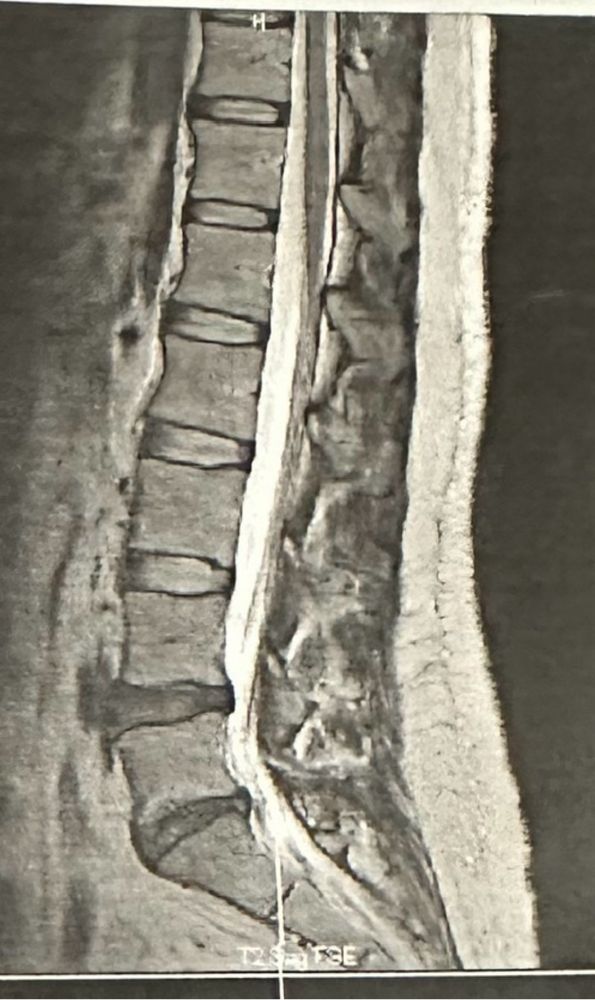

腰と足の付け根と太腿の痛み、とりあえず目立つ髄液のはみ出し方をしていなかったので、髄液が圧迫している神経に麻酔打って様子見になった。

麻酔はレントゲンとMRI合わせて、保険適用で一万ちょっと。

髄液が完全にはみ出したら、軽度ならヘルニコア、中度以上かヘルニコア使用済みなら手術になるけれど、ヘルニアは7万ぐらい、髄液を切り取る手術は十何万かかるから、財布に痛い。